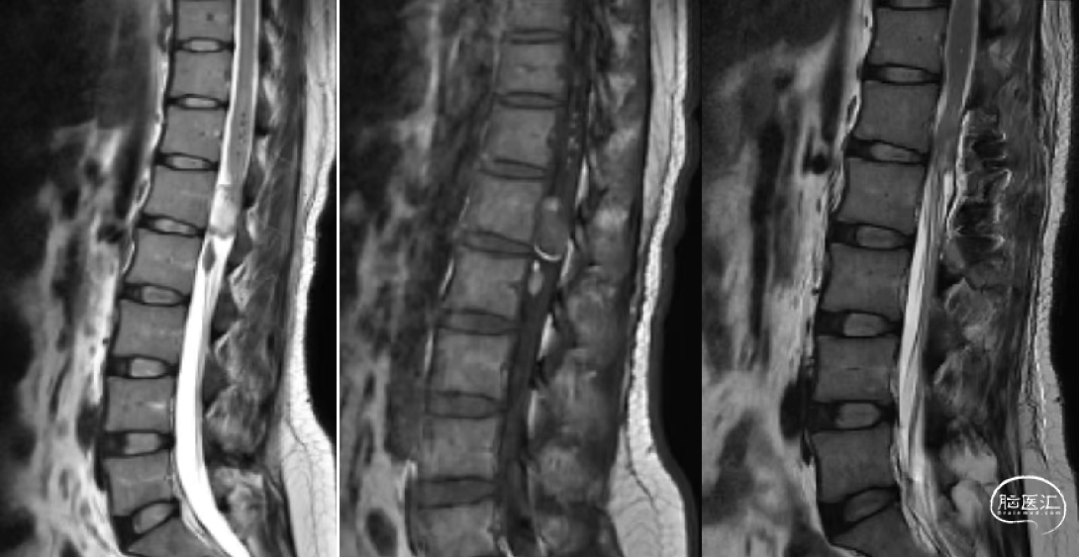

辅助检查:腰椎CT和MR示:L1-2椎管内硬膜下见一软组织信号结节,大小约24mm×12mm×10mm,T1W1低信号,T2W1稍高信号,增强扫描明显强化,但欠均匀,临近脊髓受压改变等。

术前腰椎CT和MR如下: